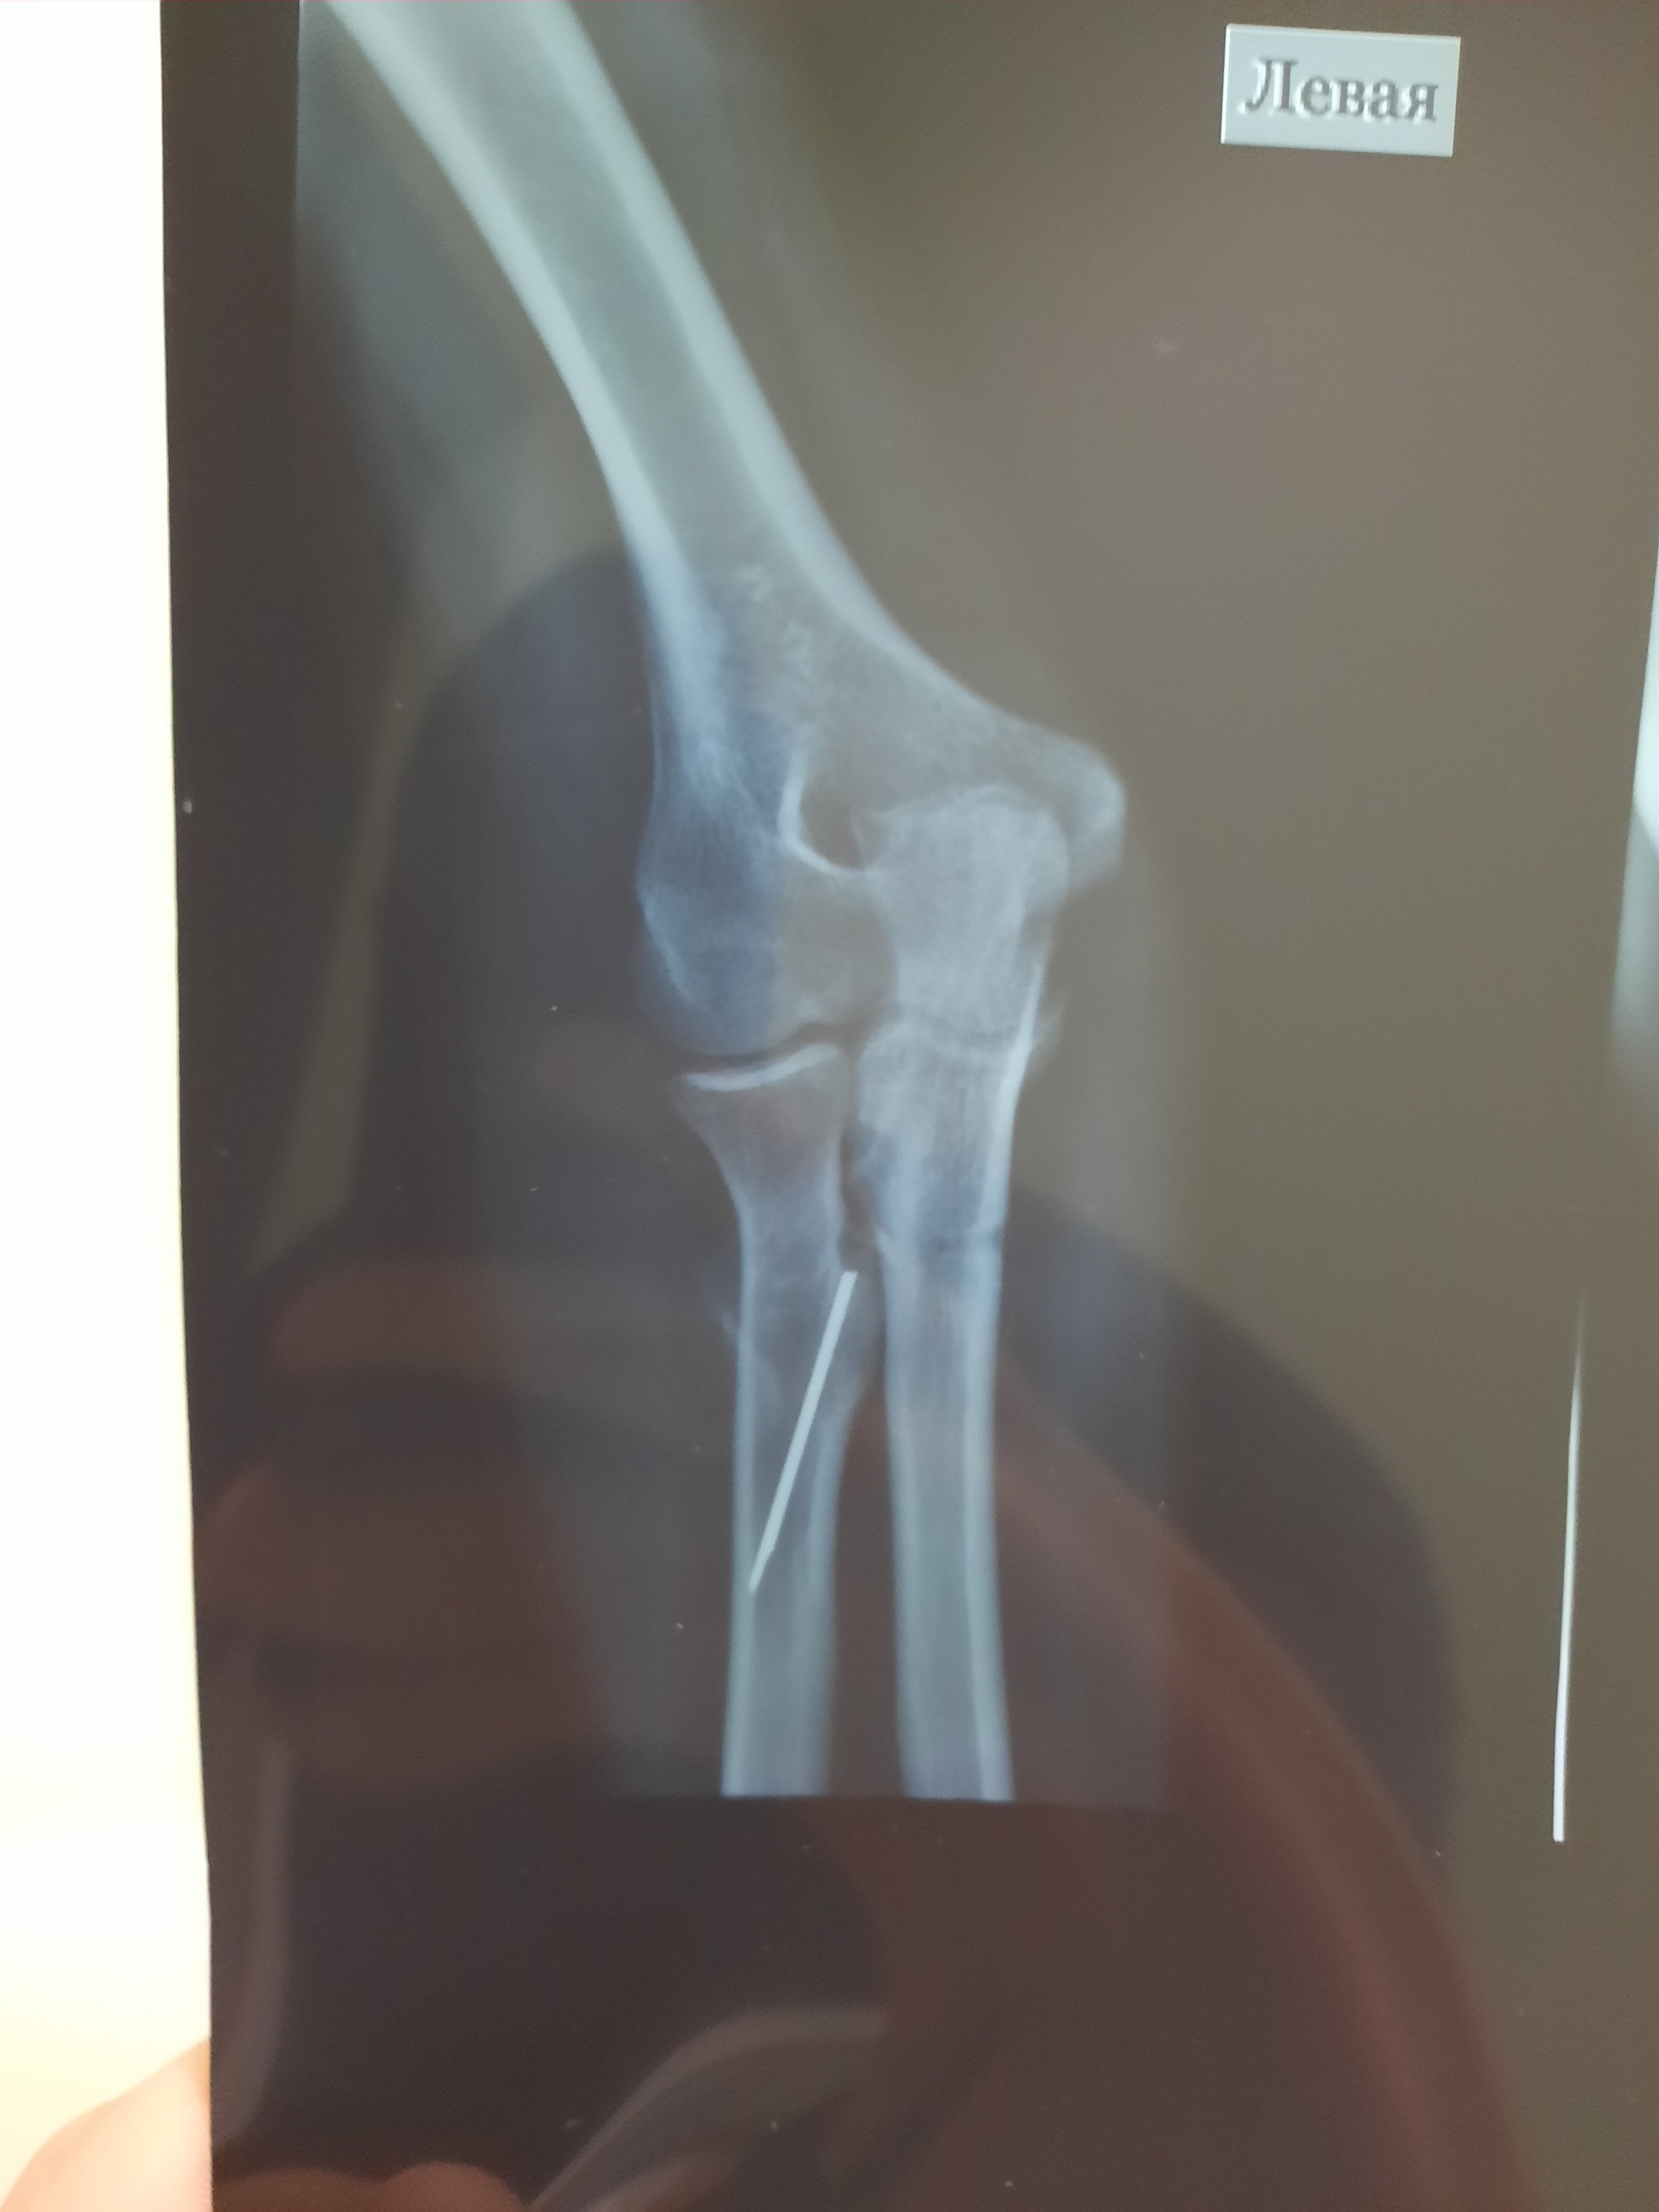

И вот три месяца назад стал жутко болеть этот палец, думаю видимо туфли неудобные купила. Но палец с каждым днем стал распухать просто жесть. Пришла я в травмпунк, мне доктор говорит "вы наверно стукнулись об угол мебели вот он и болит, ну ладно давайте я вам рентген сделаю". Я жду когда он мне результат скажет, а он выбегает злой и орёт на меня, мол "Вы почему врете то, иголку загнали в ногу и пришли как будто не знаете". Я в шоке, в голове каша, стало плохо и страшно. Столько лет иголка в ноге жила. Самое интересное что половина эта была с ушком, тобишь толстая половина иглы. Как она 16 лет сидела в ноге ума не приложу. И ведь не беспокоила ни разу. Сейчас от неё осталось напоминание в виде небольшого шва. Хируг сказал что повезло нереально как, игла была между костью и сухожилием, и воздух не попал, поэтому и не беспокоила. Вот такая история🤭